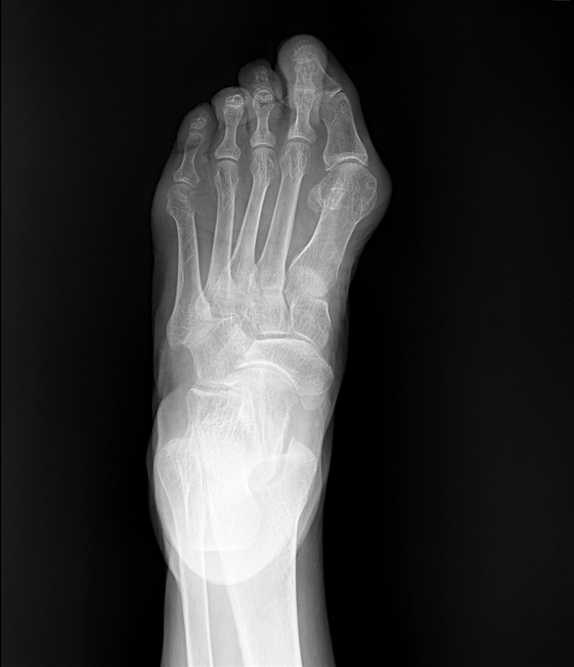

아치의 무너짐이 가져오는 평발

주요 증상: 발의 내측 아치가 낮거나 완전히 없어 발바닥 전체가 지면에 접촉

호발 연령: 선천적 또는 후천적으로 발생, 모든 연령층에서 가능

통증 패턴: 발의 내측, 아킬레스건, 발목, 심지어 무릎까지 통증이 확산될 수 있음

유발 요인: 유전적 요인, 임신, 노화, 비만, 당뇨, 류마티스 관절염

진단 방법: 발자국 검사(족문 검사), 발의 정렬 관찰, X-ray로 뼈 구조 확인

부산평발 은 발의 아치가 낮거나 완전히 사라져 발바닥 전체가 지면에 닿는 상태를 말합니다.

정상적인 발은 체중을 효과적으로 분산시키는 아치 구조가 있지만, 평발은 이러한 충격 흡수 기능이 저하됩니다.

아침에 통증이 심한 이유는 밤새 휴식으로 발의 구조가 일시적으로 안정되었다가, 아침에 다시 체중이 실리면서 발의 인대와 근육에 갑작스러운 부담이 가해지기 때문입니다.

특히 내측 종아치를 지지하는 후경골근의 피로와 염증이 아침 통증의 원인이 됩니다.